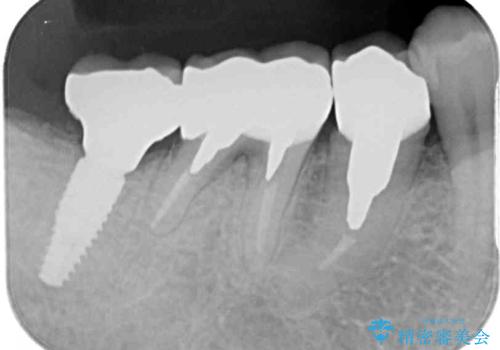

- 奥歯の欠損部へのインプラント治療を希望して来院された患者様です。

抜歯をしてから長年経過しており、レントゲンからは十分に骨があることが分かっていたため、速やかに治療を開始することとしました。

インプラント治療に当たり、手前の銀歯2本の審美回復も希望されたため、3歯のオールセラミッククラウンによる補綴治療を行うこととしました。

通常、奥歯を抜歯した状態で長年放置すると、咬み合う歯が伸びてきて、咬み合わせが乱れてしまうことが多いです。そのような場合には、部分的な矯正治療などが必要となるのですが、こちらの患者様は幸運なことに咬み合わせが乱れていなかったため、インプラント埋入から速やかに補綴治療を行うことができました。